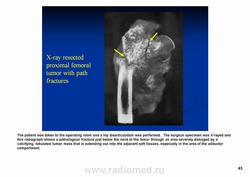

Рентгенологически выявляют в очаге деструкции участки обызвествления в виде крапчатости; кортикальный слой с признаками эрозии со стороны эндоста и истончения; размеры опухоли более 4 см; периостальная реакция слабо выражена или отсутствует; может наблюдаться деструкция кортикальной кости и наличие мягкотканного компонента; в длинных костях локализуется чаще в метафизах и диафизах; интенсивное внутрикостномозговое распространение.